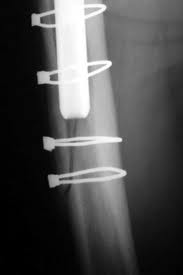

On the other hand, if the fracture extends right across the bone in a transverse or oblique direction causing the lower part of the femur to become discontinous from the upper part, then a supplemental plate fixation with bone grafting is neccessary. Purpose designed plates and cables are available for the purpose.

Impaction grafting: Impaction grafting is a technique used in revison surgery that has been devised to deal with loss of bone stock in the femur (thigh bone). The technique relies on first recreating a stable and rigid upper femur in cases with severe bone loss, using wires, wire meshes, donated bone or metal plates. In some cases all of these may be required. Once the outline “scaffold” or containment is created, donated or bank cancellous bone is inserted into the femoral tube. The bone graft is hammered into the tube recreated previously using specially shaped tamps that follow closely, the shape of the femoral component to be implanted. By this means a “new” tube is made from the bone graft material reinforced as neccessary with the metal work mentioned above. It may be difficult to believe that a bony tube made in this manner will be strong enough to take an implant, but the method does work. Once this stage of the operation is over, the surgeon will have made up the bony deficiency in the femur with the graft material and will have a bony tube with a cavity within to take the femoral component. The implant is then cemented into the cavity within the recreated femur